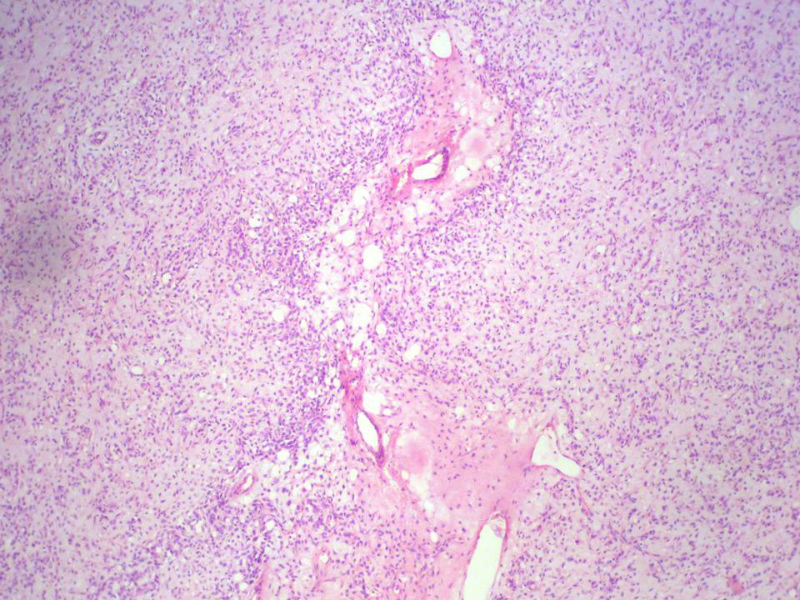

男,27岁,右股骨上段皮下肿物1年余,无明显疼痛,检查肿物明显隆起于皮下,边界清楚,手术完整切除肿物。肉眼,肿物6X6X5厘米,外观多结节状,似有包膜,切面灰白色,质韧。

特别提示:镜下核分裂3-4/HP.

3. 本例组织学改变与粘液性脂肪肉瘤,粘液样纤维肉瘤,纤维粘液样肉瘤,骨外粘液样软骨肉瘤都有重叠之处,且镜下并未见典型结构。由此,免疫组化结果就尤显重要。特别是专业书籍提到,突触素或嗜铬素阳性,对鉴别诊断有重要意义。我用CGA,也是在以上几个肿瘤中举棋不定而为。NSE和CK没用,其实我想用更多的抗体来证实更多的东西,但患者的经济条件不太好,遗憾!